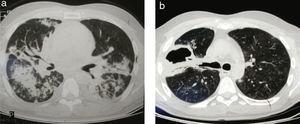

Presentamos el caso de un paciente masculino, de 35 años de edad que ingresa al servicio de clínica médica por presentar un cuadro febril asociado a tos y expectoración purulenta. La radiografía de tórax muestra opacidad basal derecha, interpretando el cuadro de ingreso como neumonía aguda de la comunidad. A las 48h de ingreso, evoluciona desfavorablemente con mala mecánica ventilatoria, requiriendo el pase a la unidad de terapia intensiva y asistencia respiratoria mecánica. Evoluciona con caída de veinte puntos del hematocrito, y falla renal asociada. Se solicita el ANCA-C y la proteinasa 3, los cuales resultan positivos, llegando así al diagnóstico presuntivo de granulomatosis de Wegener. Se inicia ciclofosfamida 500mg, y se realiza plasmaféresis. Intercurre con tos y expectoración muco-purulenta, por lo cual se realiza tomografía axial computada de tórax en la cual se evidencia infiltrado bibasal a predominio derecho (fig. 1a), iniciándose antibioticoterapia con vancomicina, meropenem y colistin. Se reinicia la plasmaféresis y se decide por buena evolución su pase a sala general de clínica médica. Intercurre con fiebre persistente, por lo cual se rota posteriormente a imipenem-colistin por aislamiento de Klebsiella Pneumoniae y Pseudomona Aeuruginosa en lavado broncoalveolar, la cual se completa durante 14 días. La evolución es favorable y se le otorga el alta hospitalaria con prednisona 60mg/día. Comienza en su domicilio con dolor de tipo puntada de costado asociada a disnea, por lo cual acude a la guardia, constatándose en radiografía de tórax neumotórax derecho grado II, decidiéndose realizar avenamiento pleural bajo agua. Evoluciona desfavorablemente, con enfisema subcutáneo y fístula broncopleural persistente con aerorragia y débito purulento. Se solicita tomografía axial computada que muestra pioneumotórax y masa pulmonar abscedada y cavitada en el lóbulo superior derecho (fig. 1b). Ante la persistencia del débito purulento y la falla de expansión pulmonar, se decide conducta quirúrgica. Se aborda por toracotomía posterolateral y se identifica granuloma abscedado y fistulizado hacia pleura de 11cm de diámetro ubicado en el lóbulo superior derecho (fig. 2a). Se realiza la resección completa del mismo con sutura mecánica (fig. 2b), completando la cirugía con decorticación pulmonar (fig. 2c). Cursa postoperatorio inmediato en unidad de terapia intermedia durante 48h, pasando luego a sala general y otorgándole el alta hospitalaria al 6.° día postoperatorio en buena evolución. El informe histopatológico diferido de la pieza quirúrgica (fig. 2d) confirmó el diagnóstico de granulomatosis de Wegener.